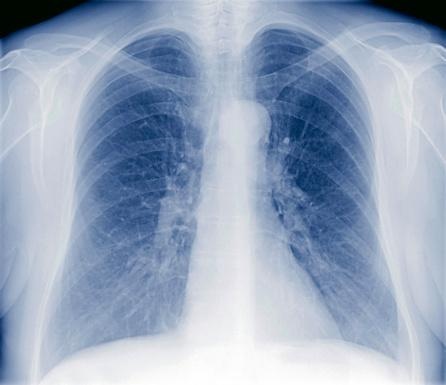

Solange die Erkrankung auf die Haut beschränkt bleibt, sie wird dann Sklerodermie genannt, gefährdet sie das Leben der Patienten nicht. Doch schon im August litt die Frau bei leichteren körperlichen Anstrengungen unter Luftnot. Im Oktober waren in einer Computertomografie die typischen Veränderungen einer sog. Lungenfibrose zu erkennen. „Das Bindegewebe in den Lungen hatte sich auch weiter verhärtet, und es drohte eine zunehmende Einschränkung der Sauerstoffversorgung“, berichtete Dr. Merkt: „Wir behandelten sie deshalb mit Cyclophosphamid, später auch Mycophenolat, zwei starken Immunblockern“. Als sich keine Besserung abzeichnete, erhielt die Patientin ab März 2022 noch ein weiteres Mittel (Nintedanib), das die Narbenbildung (Fibrose) in den Lungen stoppen sollte. Vergeblich. Dr. Merkt sagt: „Die Erkrankung schritt rasch voran und hätte auf absehbare Zeit das Leben der Patientin gefährdet.“